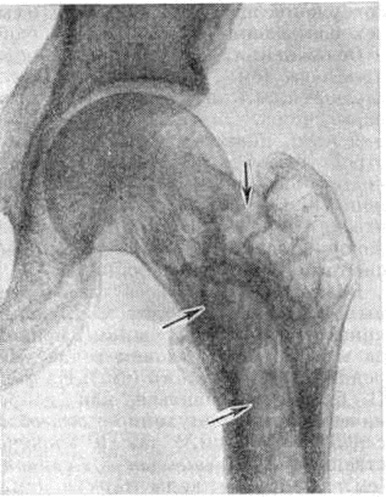

Рис. 10.

Рентгенограмма тазобедренного сустава больного с болезнью Педжета: структура межвертельной области бедренной кости имеет грубый вид, ячейки (указаны стрелками) между костными перекладинами крупные, неправильной формы.

Ранние этапы болезни рентгенологически характеризуются изменениями внутренней архитектоники кости, затем к ним присоединяются утолщение и деформация кости. Наиболее характерна для Педжета болезнь видимая на снимках груботрабекулярная перестройка костной структуры. Костные перекладины утолщаются, группируются в пучки, вследствие чего вся структура кости приобретает грубый вид, ячейки между костными перекладинами становятся крупными, неправильной формы, костные перекладины в основном сохраняют свою функциональный направленность (рисунок 9—11). В процесс перестройки вовлекается и корковое вещество, которое приобретает волокнистый вид; в дальнейшем граница между корковым и губчатым веществом вовсе теряется, кость на уровне поражения утолщается, деформируется (рисунок 12). Целость контуров кости всегда сохраняется. Утолщение трубчатых костей сочетается с сужением костномозгового канала, а затем и полным его исчезновением. Структура поражённого участка кости по всей его толщине становится одинаковой. Кости черепа могут утолщаться в 2—3 раза. Структура их на рентгенограмме отличается своеобразным хлопьевидным рисунком вследствие неравномерной перестройки с чередованием участков уплотнения и разрежения костного вещества. В позвоночнике, как правило, поражается тело позвонка, но процесс перестройки может распространиться и на дугу. Структура позвонка становится грубой, крупноячеистой, основные пучки балок располагаются по сторонам в виде рамы. Тело позвонка всегда увеличено в боковых и переднезаднем направлениях, высота его снижается, реже остаётся обычной.

Перестраивающиеся длинные трубчатые кости постепенно искривляются, с выпуклой стороны нередко развиваются зоны патологической функциональной перестройки (смотри полный свод знаний: Лоозера зоны), на основе которых возникают характерные так называемый банановые переломы, проходящие поперечно к продольной оси кости и имеющие ровную, иногда изогнутую поверхность (рисунок 13).